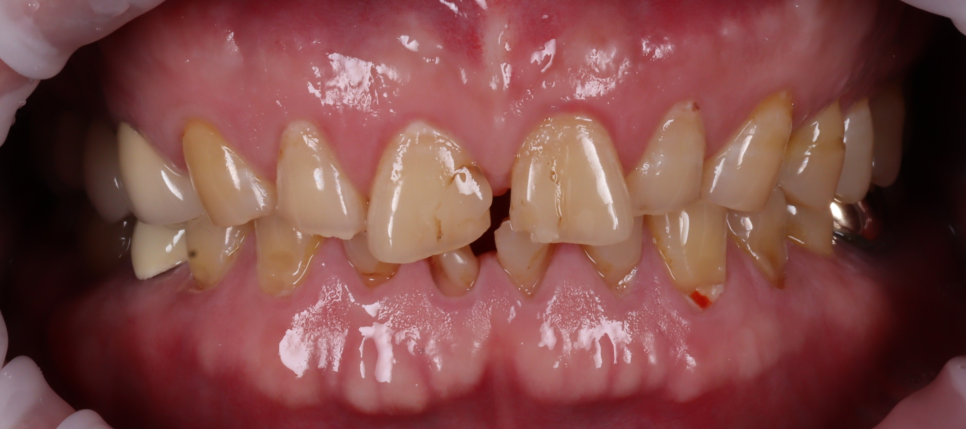

아랫니가 많이 닳아서 이를 다물면 거의 안 보여요. 신논현역치과 앞니가 심하게 닳아 저희 치과로 오신 분이셨어요. 감사하게도 수원에 있는 종합병원에 계시는 치과 과장님의 소개를 받아 서울까지 내원해 주셨더라고요ㅎㅎ 치아를 오랫동안 사용하다 보면 누구나 조금씩 닳는데요. ...

출처 아카이브 열기아랫니가 많이 닳아서

이를 다물면 거의 안 보여요.

앞니가 심하게 닳아 저희 치과로 오신 분이셨어요. 감사하게도 수원에 있는 종합병원에 계시는 치과 과장님의 소개를 받아 서울까지 내원해 주셨더라고요ㅎㅎ

깊게 물리는 교합으로 이미 많이 닳아버린 앞니들

촬영일 : 251013

아래 앞니는 치아 윗부분(절단면)이 많이 닳아서 길이가 눈에 띄게 짧아져 있었고, 닳아 없어지면서 사이사이에 빈 공간이 보였어요.

뿐만 아니라, 치아 겉 부분(법랑질)이 모두 닳아 신경과 가까운 상아질이 모두 노출되어 있었는데요.

이렇게 상아질이 노출되어 있으면 시린 증상이 나타나며, 장기간 지속될 경우 신경까지 괴사될 수 있어 치료가 시급한 상황이었습니다.

또, 아랫니가 많이 닳아있어 깊게 무는 형태인 'Deep bite(딥바이트)' 라고 부르는 과개교합 상태였죠.

오랜 시간 서로 부딪히며 위아래가 서로를 갈아버린 흔적이죠.

양쪽 작은 어금니 쪽에는 잇몸 가까이 패인 마모 부위도 있었고 찬물이나 칫솔질 때 "시큰시큰하다"라고 하셨어요.

환자분은 “아래 앞니가 많이 닳았어요"라고 말씀하셨지만 실제로는 아래 앞니에만 문제가 있는 것이 아니라 전체적인 교합, 마모 패턴을 같이 봐야 하는 상황이었어요.